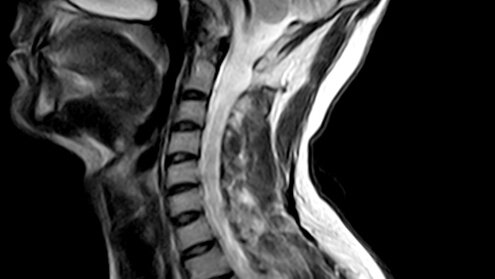

Что показывает МРТ шеи - процедура и расшифровка

МРТ шеи - это собирательное обозначение разных томографических обследований шейно-воротниковой зоны. Оно может подразумевать: МРТ шейного отдела позвоночника с контрастом или без. Магнитно-резонансное исследование сосудов шеи (или МР-ангиография шеи)...